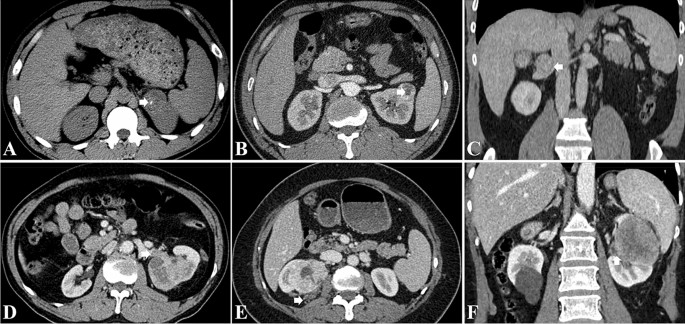

The presence of collateral vessel was defined as asymmetrically increased, usually irregular vessel within Gerota’s fascia or renal hilum of the kidney11, collateral arteries and veins were identified on the CMP and NP images, respectively (Fig. 2). The following imaging features were recorded: tumor size (maximal diameter), tumor location, the presence of calcification, necrosis, perirenal fat invasion, renal sinus invasion, renal vein invasion and thrombus (Fig. 3)8,32. Tumor attenuation and the tumor-to-renal contrast were quantitatively assessed. For heterogeneous lesions, a round or elliptic ROI was placed in the area that had the greatest degree of enhancement of the renal tumor in the CMP and NP; for homogeneous lesions, ROIs were placed in the center of the renal tumor33. The ROIs measured approximately 0.2–1 cm2 and were consistent in size and location on the unenhanced phase, CMP and NP images32. ROIs were also placed in the adjacent normal renal cortex for normalization33. At least three measurements were performed for each lesion and renal cortex on three CT scans, with averaged results34. The tumor-to-renal contrast was measured by subtracting the tumor attenuation from the normal renal cortex attenuation during the unenhanced phase, CMP and NP, respectively.

CT imaging features as assessed by both readers: (A) calcification; (B) necrosis; (C) renal vein invasion; (D) renal vein thrombus; (E), perirenal fat invasion; (F) renal sinus invasion.